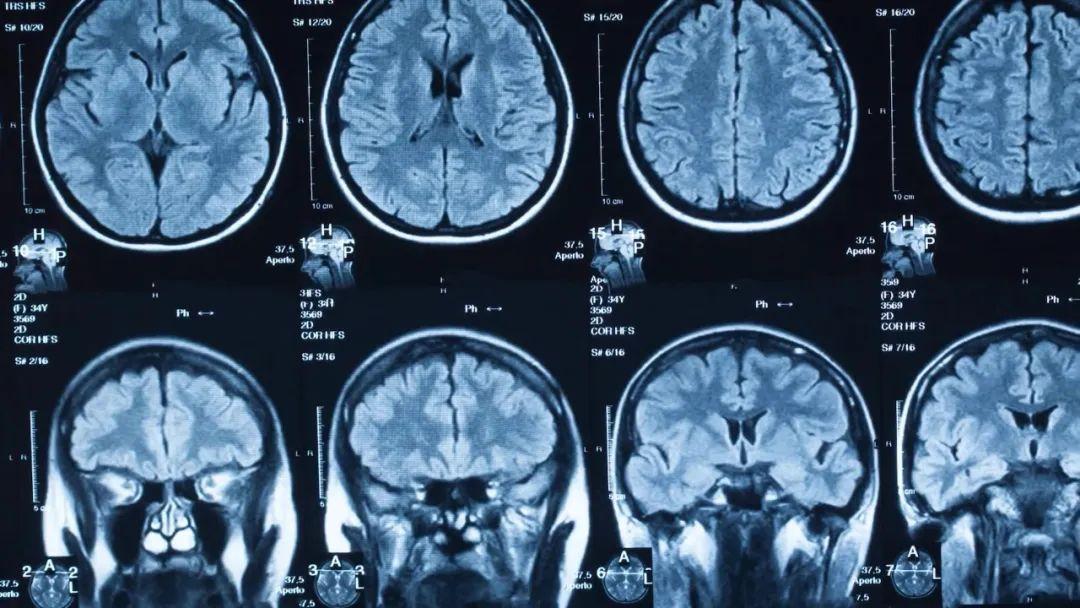

对于人体中的核磁共振成像,通常以氢核为目标,因为其中水和脂肪中有很多,然后图像的亮度基本上可以告诉我们脂肪和水的数量。人们也可以瞄准其它原子核并进行测量,这就导致了不同核磁共振图像的工作方式不同。核磁共振成像非常适合于检查软组织,而对于骨折一般则使用X射线成像。

上述提到,共振频率与磁场强度成正比,正因为如此,我们可以使用磁场梯度来瞄准特定位置的原子核,生成不同位置的身体切片图像。